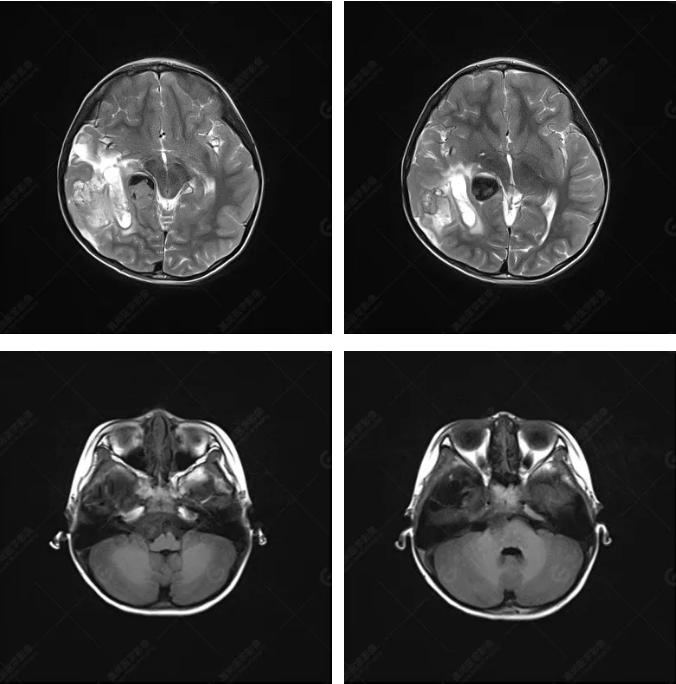

右側(cè)顳葉腫瘤切除術(shù)后(具體不詳):右側(cè)顳部骨質(zhì)不連續(xù)呈術(shù)后改變,右側(cè)顳葉術(shù)區(qū)見片狀長T1長T2信號影,F(xiàn)LAIR呈低信號;術(shù)區(qū)后方右側(cè)顳枕葉見一巨大占位性病變影,邊界欠清,大小約6.2×5.8×4.3cm(前后×左右×上下),信號不均勻,T1WI呈等稍低信號間雜少許高信號,T2WI呈高稍低混雜信號,DWI示部分病灶彌散受限,相應(yīng)ADC圖減低,磁敏感序列見部分呈極低信號,增強掃描可見明顯不均勻強化,鄰近硬腦膜及小腦幕增厚并明顯強化;另延髓右前方及右側(cè)橋小腦角區(qū)見一不規(guī)則形異常信號影,大小約3.2×1.3×3.7cm(左右×前后×上下),呈長T1稍長T2信號,F(xiàn)LAIR呈等信號,DWI未見受限,增強后明顯均勻強化,鄰近腦膜明顯強化。鄰近腦實質(zhì)及右側(cè)顳角明顯受壓;左側(cè)大腦半球未見局灶性信號異常,中線結(jié)構(gòu)稍左移。

右側(cè)顳葉腫瘤切除術(shù)后:現(xiàn)術(shù)區(qū)后方右側(cè)顳枕葉及延髓右前方占位,右側(cè)顳枕部硬腦膜及小腦幕明顯強化,結(jié)合既往影像資料,考慮為胚胎源性惡性腫瘤,如非典型畸胎樣/橫紋肌樣瘤(AT/RT)或原始神經(jīng)外胚層腫瘤(PNET)。